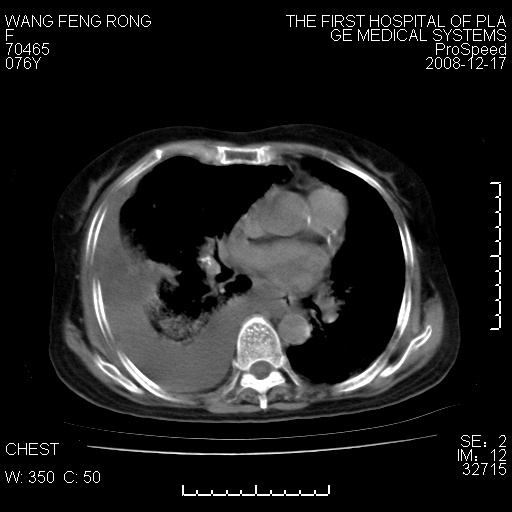

右肺大部实变,其内可见支气管影,但分支减少,宽窄不均,走行僵直,同侧胸腔大量积液;纵隔内见多发淋巴结影,但淋巴结大部有钙化;主动脉壁钙化;临床上病人咳嗽、消瘦。所以我考虑:1、结核(依据:右下肺实变,纵隔内淋巴结符合结核表现,同侧并发胸膜炎表现);2、支气管肺泡癌(依据:实变的肺组织内支气管分支减少,宽窄不均,走行僵直,没有把它放在第一诊断是因为没有看到明显肿大的淋巴结);3、动脉硬化(主动脉壁钙化就支持这个诊断)。

1)考虑两肺炎症感染;不排除肺泡癌可能。2)两肺间质纤维化。3)右侧胸腔积液。

病理结果,肺泡癌